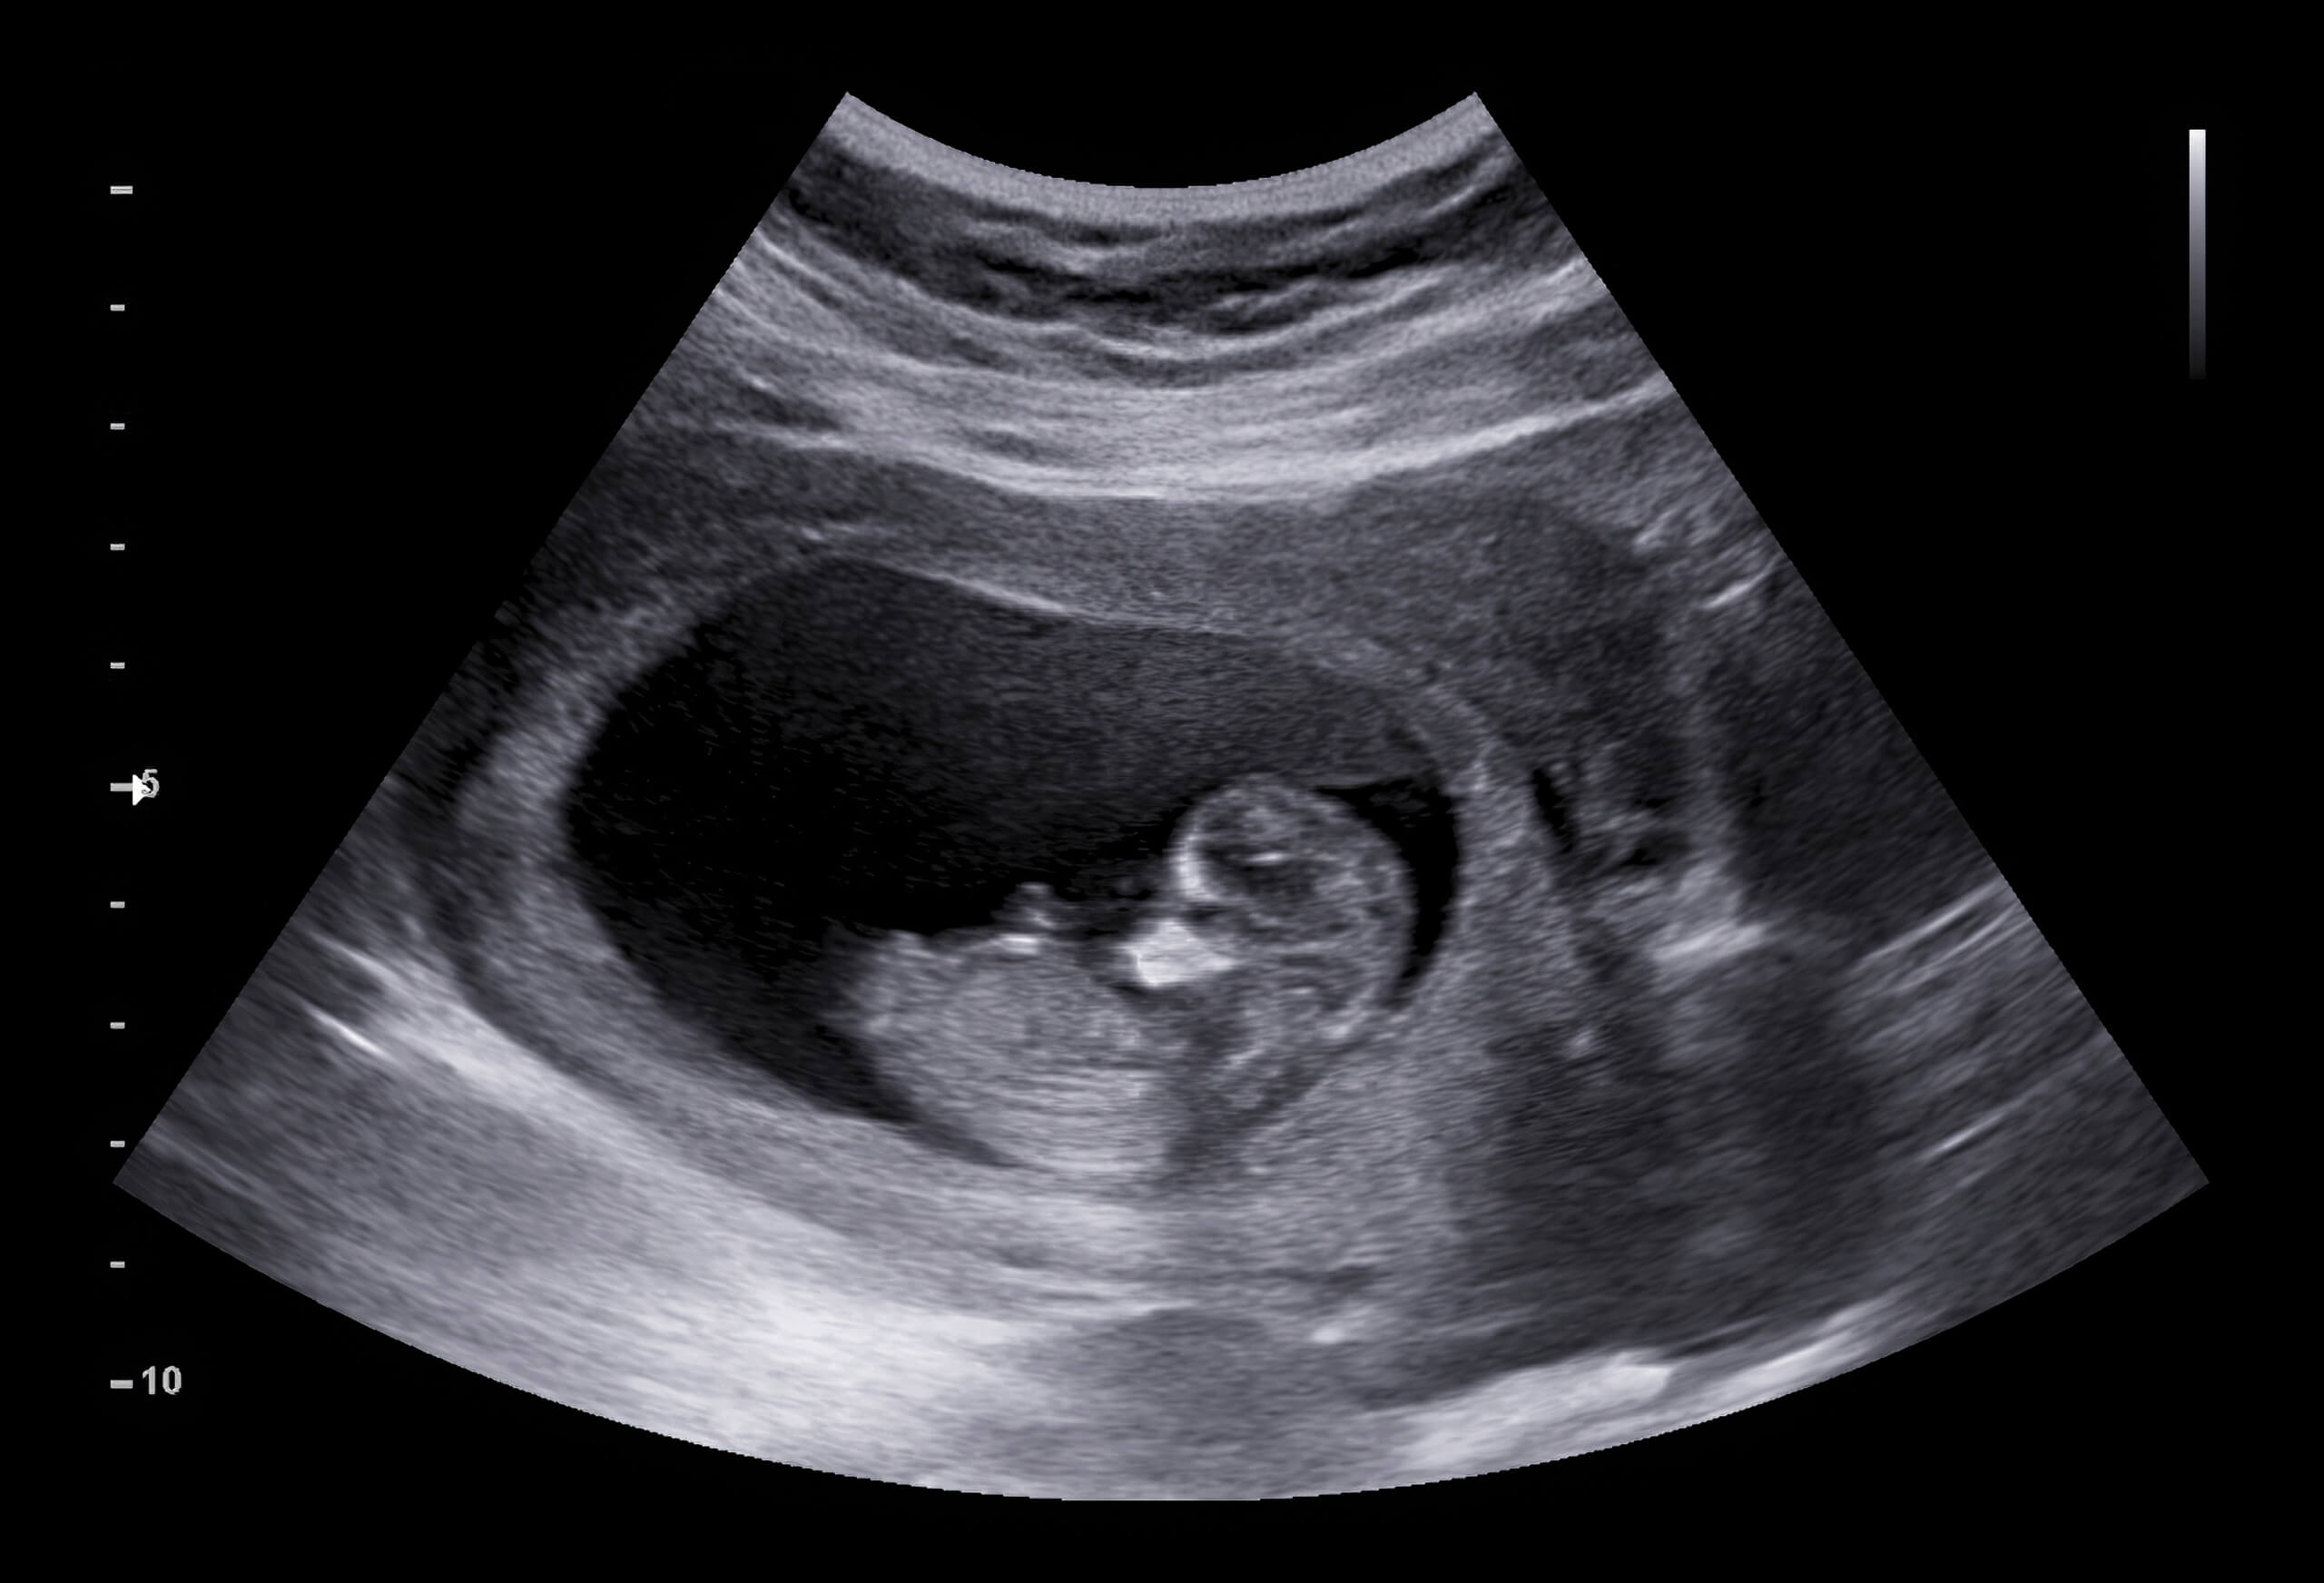

But that excitement soon turned into fear. During one of my routine prenatal checkups, the doctor scheduled an ultrasound to check on the baby’s development. At first, everything seemed normal, but as the doctor studied the screen, his expression changed. He became quiet, then serious. My heart started racing.…CONTINUE READING